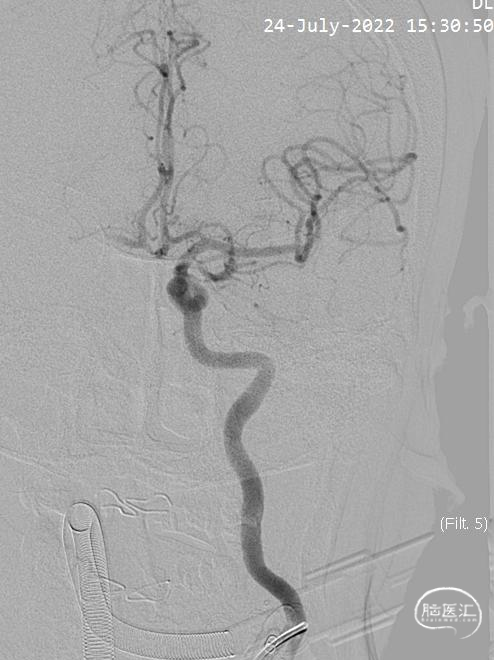

左侧颈内动脉造影示:经前交通向右侧大脑前动脉供血。

右侧颈内动脉造影示:后交通动脉以上颈内动脉闭塞。

术前正位造影。